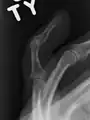

Le diagnostic est généralement basé sur les symptômes et confirmé par des radiographies[1]. La lésion peut être accompagnée d'un œdème et d'une ecchymose[3].

Radiographie montrant une fracture à l'insertion du tendon extenseur